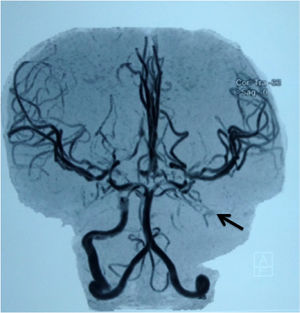

All the eight children being started on the RTP due to significant MRA abnormalities (Table 2, Figure 2) concomitantly used HU. The RTP was discontinued in two patients, one due to alloimmunization, with no compatible blood regularly available, and the other because a new MRA 1.5 years after the first showed abnormality reversal and three consecutive TCD studies showed a low risk for stroke. Both patients were treated with HU. None of the eight children had a stroke over the clinical follow-up.

Children submitted to the primary prevention program after inconclusive transcranial Doppler and diagnosis of being at high risk for ischemic stroke by abnormal magnetic resonance angiography (MRA) images.

| Children | Age at 1st TCD (years) | Abnormalities in MRA or MRI |

|---|---|---|

| #1 | 3.7 | 07/2016 - MRA: partial occlusion of the proximal segment M1 of the left middle cerebral artery. 06/2018 - MRA: no abnormality. 07/2016- MRI: no abnormality |

| #2 | 3.0 | 09/2013 - MRA: stenosis of the left internal carotid artery; vascular proliferation type moyamoya. 07/2015 - MRA: stenosis of the right internal carotid artery and moyamoya syndrome |

| #3 | 3.4 | 10/2018 - MRA: stenosis of both internal carotid artery, anterior cerebral arteries and middle cerebral arteries; moyamoya syndrome. MRI: gliosis and silent infarcts |

| #4 | 7.5 | 05/2015 - MRA: moyamoya syndrome |

| #5 | 7.6 | 04/2012 - MRA: stenosis of left internal carotid and carotid bifurcation |

| #6 | 4.3 | 08/2013 - MRA: severe stenosis of the right internal carotid artery and occlusion of the left internal carotid artery. 10/2015: MRA: occlusion of the internal carotid arteries. 09/2018: MRA: severe vasculopathy |

| #7 | 2.6 | 05/2017 - MRA: stenosis of both internal carotid arteries and moyamoya syndrome. MRA - 02/2019: progression of vasculopathy; probable silent infarct and moyamoya syndrome |

| #8 | 4.4 | 02/2009 - MRA: stenosis of both middle cerebral arteries + moyamoya syndrome. Areas of left frontoparietal cerebral softening, probably related to prior stroke |

| #9* | 3.8 | 03/2014 - MRA: stenosis of both middle cerebral arteries + moyamoya syndrome |

Magnetic resonance angiography in the child #6 (Table 2), showing occlusion of the left internal carotid artery (arrow).